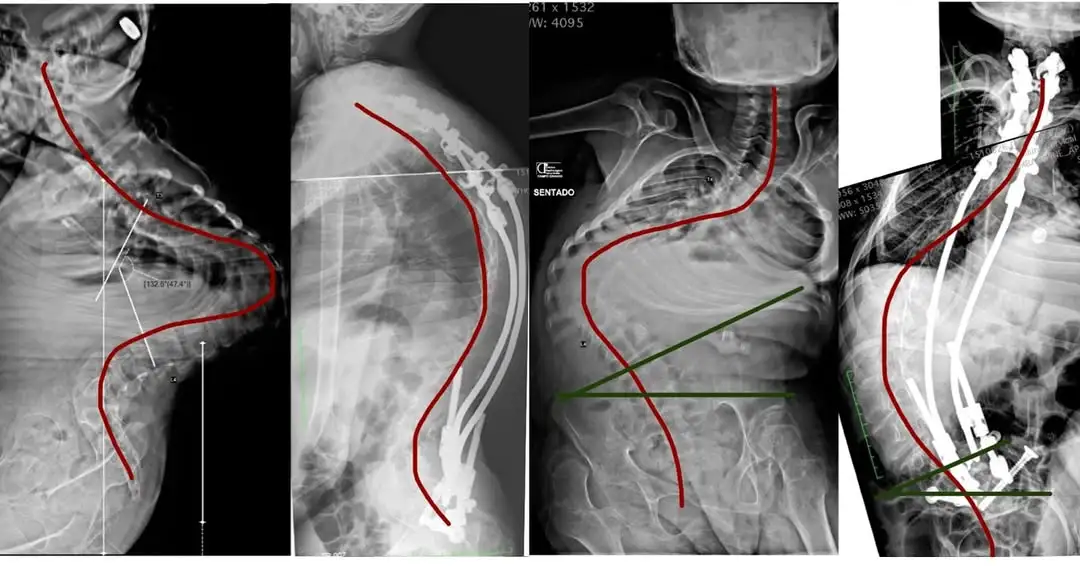

O que é a técnica bipolar?

A técnica bipolar é um tipo de cirurgia utilizada no tratamento da escoliose, principalmente em duas situações: crianças pequenas que ainda estão crescendo e pacientes frágeis, como aqueles com escoliose neuromuscular, paralisia cerebral, distrofias musculares e outras condições genéticas.Diferente da cirurgia tradicional — que exige abrir toda a extensão da coluna, colocar parafusos em todas as vértebras necessárias e instalar duas hastes completas — a técnica bipolar utiliza somente dois pontos de fixação: um na parte superior e outro na parte inferior da coluna.Entre esses pontos, utiliza-se um dispositivo de crescimento, permitindo que a coluna continue a se desenvolver ao longo dos anos.

Como funciona a técnica bipolar?

A técnica bipolar utiliza dois “blocos” de fixação — um superior e um inferior — e um sistema que permite o crescimento natural da coluna entre esses pontos.Em muitos casos, utiliza-se o dispositivo de crescimento chamado Nemost, que funciona como um “macaco de carro”: conforme a criança cresce, ele se estende, mas não volta.Existem duas abordagens:- Técnicas tradicionais de crescimento: exigem retorno ao centro cirúrgico a cada 3 a 9 meses para alongamento.

- Técnica bipolar com Nemost: permite que o crescimento aconteça sozinho, reduzindo o número de cirurgias.